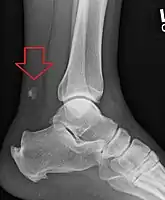

Radiography can also be used to indirectly identify Achilles tears. Radiography uses X-rays to analyse the point of injury. This is not very effective at identifying injuries to soft tissue. X-rays are created when high energy electrons hit a metal source. X-ray images are acquired by utilising the different attenuation characteristics of dense (e.g. calcium in bone) and less dense (e.g. muscle) tissues when these rays pass through tissue and are captured on film. X-rays are generally exposed to optimise visualisation of dense objects such as bone while soft tissue remains relatively undifferentiated in the background. Radiography has little role in assessment of Achilles' tendon injury and is more useful for ruling out other injuries such as calcaneal fractures.[13]

Achilles tendon avulsion seen on plain X-ray

Achilles tendon rupture seen on ultrasound. Note discontinuity over several centimeters (red line). No fracture or avulsion (radiograph).